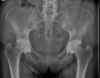

Masculino, 12 anos

Síndrome da sincondrose isquiopúbica assimétrica (Doença de Van Neck-Odelberg)

Variante da normalidade (em geral assintomático)

Crianças

Alargamento e radioluscência na sincondrose isquiopúbica, que simula neoplasias, infecção;